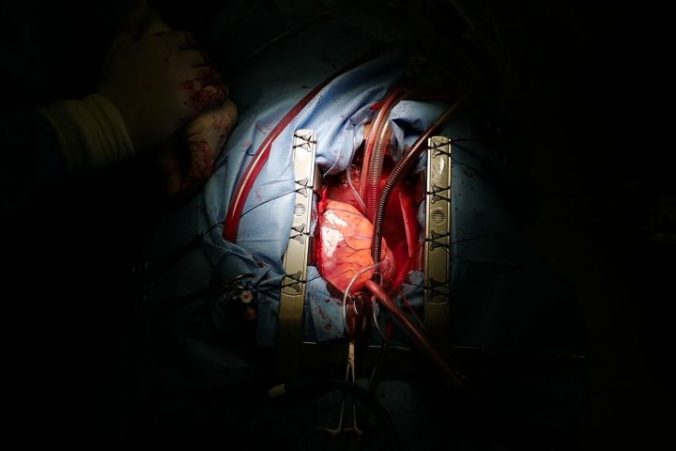

Srdce pacienta pred vyňatím Zdroj: NÚSCH

Srdce pacienta pred vyňatím Zdroj: NÚSCH